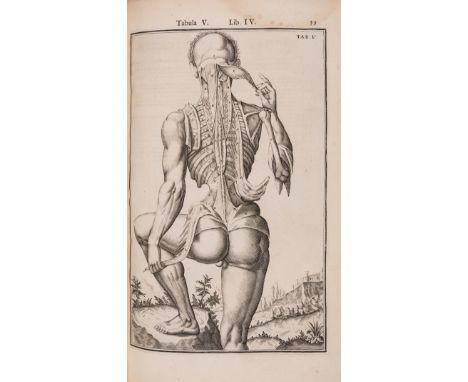

NO RESERVE Anatomy.- Spieghel (Adriaan van den) Opera quae extant omnia, edited by J.A. vander Linden, 2 parts in 1, first collected edition, with engraved architectural title by Francesco Valesio after Viallet, engraved portrait by Falck and c.110 engraved full-page illustrations only (of 117), also lacking half-title, title to vol.1, Ii3-4, 2 K3, and R4 from vol.2, woodcut initials and ornaments, a few leaves loosely inserted, water- and damp-staining, mostly at beginning and end or marginal, images generally clean, slight worming towards end, contemporary calf, worn, Amsterdam, Johannes Blaeu, 1645; and another defective disbound copy of the same but with some of the leaves missing from the first, folio; sold not subject to return (2)